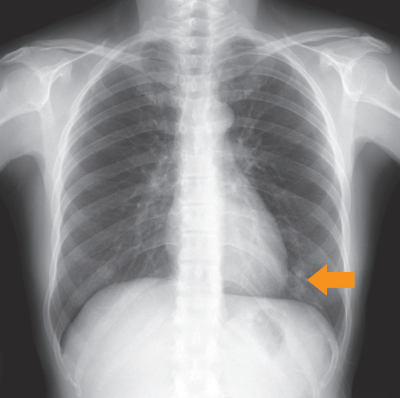

血液所見:赤血球428万、Hb 12.1 g/dL、Ht 37%、白血球 3,700、血小板 19万。血液生化学所見:総蛋白 7.2 g/dL、アルブミン 4.1 g/dL、クレアチニン 0.6 mg/dL、HbA1c 5.8%(基準 4.6~6.2)。胸部エックス線写真で左下肺野に矢印で示す結節影を認めたため、入院精査の方針となった。選択的肺動脈造影と胸部単純CTを別に示す。